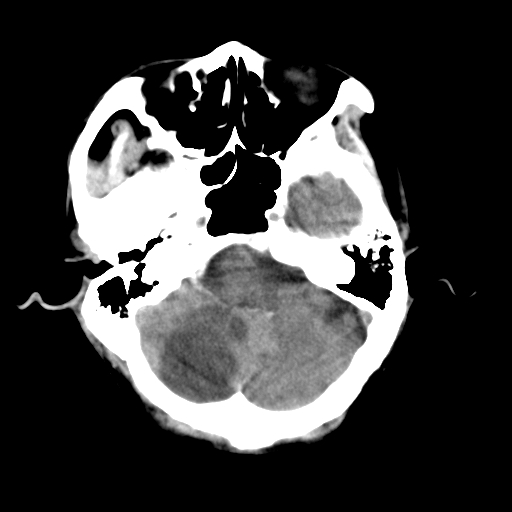

标题: CT25306:男性,75岁。右侧肢体无力一周。 [打印本页]

标题: CT25306:男性,75岁。右侧肢体无力一周。

右侧小脑楔形片状低密度影,考虑脑梗塞,建议mri或增强检查除外肿瘤占位

1)右侧小脑梗塞。2)脑萎缩。

右侧小脑梗塞!支持